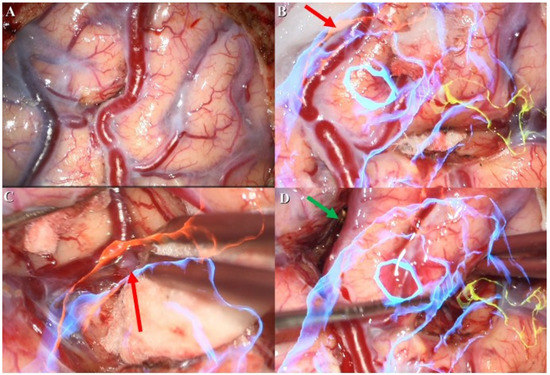

An adult patient was brought to our emergency department due to a falling accident. According to a witness, this patient suffered from a sudden change in consciousness, followed by a 3 m height fall while working. Upon arrival at our emergency department, his Glasgow Coma Scale (GCS) was E4V5M6, without any signs of specific neurological deficit. A review of his medical history showed that he had an incidental right parietal lesion with hemorrhagic vestige (Figure 1A) which was revealed through computed tomography(CT) 6 months earlier during a hospital visit for intermittent headaches. No weakness in extremities or neurological deficit was noted during this period.

Diagnostic workup involving magnetic resonance imaging (MRI) and magnetic resonance angiography (MRA) revealed a lesion with a tangle of vessels (Figure 1B) presenting itself with a signal void appearance in the right parietal region on a T2-weighted (Figure 1C) series. In addition, the Spetzler–Martin grade I AVM (size < 3 cm, superficial drainage, non-eloquent cortex) revealed evidence of a rupture with hemorrhage. The main arterial supply was comprised in the right terminal branch of the posterior cerebral artery and the parietal branch of the middle cerebral artery, with superficial drainage into cortical vein superiorly.

The first stage of the operation for the patient’s AVM resection was confirmative digital subtraction angiography (DSA) (Figure 1D) followed by right parieto-occipital craniotomy. After performing a dura opening, surgery proceeded to the microsurgical stage performed under a microscope (Figure 2A). With assistance from the AR technique, the feeding arteries from the posterior cerebral artery and the parietal branch of the middle cerebral artery were labeled with red and yellow color, respectively, and then projected onto the cortex. Furthermore, the AVM nidus was coded with blue color for identification (Figure 2B). In the next dissection and resection stage, we adjusted the focal length and hologram setting to clarify the surgical field. After confirmation of the spatial relationship in the angiographic complex, both coagulation and clipping were performed to obliterate the feeding artery (Figure 2C). After the clipping and coagulation of the first feeding artery from the middle cerebral artery, we proceeded to obliterate another feeding artery from the posterior cerebral artery (Figure 2D). Eventually, the AVM nidus got resected after both the feeding arteries were obliterated.

Figure 1. Preoperative and intraoperative images. (A) Right parietal suspected vascular lesion with hemorrhagic vestige from computed tomography (CT) (blue arrow). (B) Preoperative reconstructive magnetic resonance angiography (MRA) revealed the tangled vascular lesion (red arrow) (C) Flow voiding phenomenon was noted from T2-weighted image (green arrow). (D) Intraoperative digital subtraction angiography (DSA) for confirmation of lesion location.